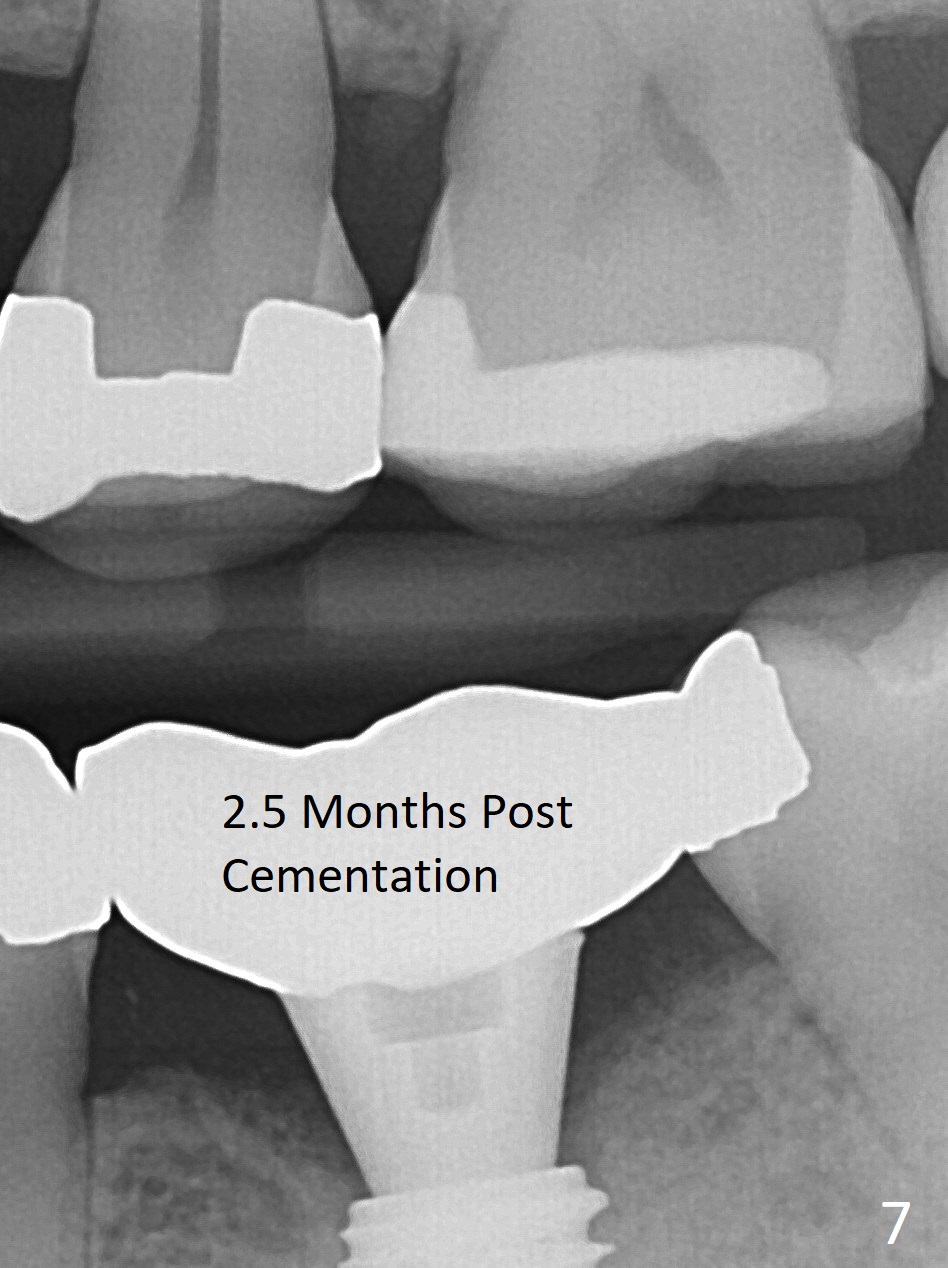

The ridge at #19 is slightly atrophic 5 months post socket preservation (Fig.1). The bone is long enough to hold a 11.5 mm long implant. There is no difficulty in inserting the corresponding drill (4.5x11.5 mm) into the metal sleeve, but the lower right posterior teeth prevent the implant handpiece from going downward completely when the handpiece accesses lingually. Because of the extra manipulation, a 5x10 mm implant achieves insertion torque of ~ 20 Ncm (Fig.2). The implant seems to be seated in the middle of the ridge (Fig.3). The bone density mesial to the implant increases 5 months postop (Fig.4), whereas that distal to the implant remains low 9 months postop (Fig.5). Bitewings taken 2.5 months post cementation (1 year postop, Fig.6,7) show subcrestal placement of the implant (advantage of guided surgery). The implant appears to be well protected; the crestal bone seems to cover the implant plateau. There will be little chance of thread exposure over years of use. The trabecular pattern around the implant is similar to that around the roots of the tooth #30 one year 7 months post cementation (2 years 4 months postop, Fig.8).